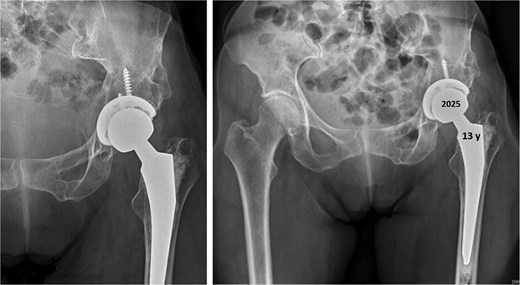

In 1984, a 35-year-old female patient presented to our department with severe left groin pain. Preoperative pelvic radiographs revealed acetabular dysplasia with subluxation at Crowe Grade I and Tönnis Grade I. A Pol Le Cœur corrective TPO was performed (Fig. 1). Over the following 28 years, radiographic examinations demonstrated progressive articular degradation despite the initial clinical success of the osteotomy.

Postoperative anteroposterior radiographs of the pelvis, showing Pol Le Cœeur triple pelvic osteotomy performed on a 35-year-old female patient to treat an acetabular dysplasia in the left hip, at Grade 1 Crowe’s classification.